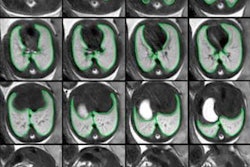

In clubfoot, the main risk factors are family history, intrauterine position, neuromuscular disorders, and oligohydramnios. Fetal MRI highlights malpositioning of the foot in thick slab T2-weighted sequences, explained the group. The second author of the RSNA e-poster, Dr. César Martín, is a senior pediatric radiologist who has worked on fetal MRI since 1997.

"Limbs (in hemimelia cases) are evaluated better in 3D T2-weighted HASTE [half-Fourier acquisition single-shot turbo spin-echo] sequences," González López noted.